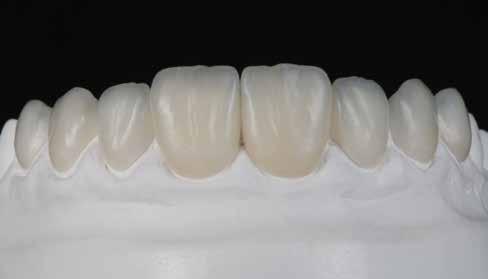

A minta beolvasása után számítógéppel terveztük meg a híd vázát (7. kép). 0,06 mm-es cementrést terveztünk a teljes karfelület alá, 1 mmre végződve a preparáció szélétől (8–11. képek)

Így egyenlítettük ki a kötésjavító vastagságát, sikeresen. Az adatokat elküldtük az AHRtec-frézközpontba, néhány nap múlva visszakaptuk a cirkonvázat (12. kép). A marási paraméterek optimális betartása következtében a passzítás egyszerű volt (13. kép)